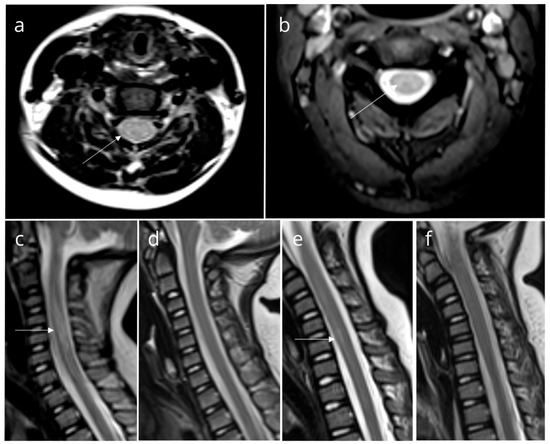

| Patient 1 | F | 2 years and 3 months | Fever, vomiting, rash on the gluteal region and upper extremities, arm twitching, ataxia | 235 | 68 | 32 | 0.43 | + | − | − | Echovirus 4 | Transverse myelitis (C1 to C6), hyperintense signals in posterior pons and medulla oblongata | IVIg (2 g/kg) Methylprednisolone (pulse doses 15 mg/kg/day of for 3 days, followed by taper-off), and plasmapheresis (4 cycle) | Full recovery |

| Patient 2 *** | F | 2 years and 8 months | Fever, vomiting, headache, tremor, ataxia, transient behavioral issues | 533 | 25 | 75 | 0.54 | + | − | − | Enterovirus 71 | Transverse myelitis (C1 to C7) | IVIg (2 g/kg) Methylprednisolone (pulse doses 20 mg/kg/day for 3 days, followed by taper-off) | Full recovery |

| Patient 3 *** | F | 1 year and 8 months | Fever, vomiting, headache, tremor, ataxia, maculopapular rash | 1110 | 70 | 30 | 0.63 | − | − | + | Enterovirus 71 | Transverse myelitis (C4 to C6) | IVIg (1.5 g/kg) | Full recovery |

| Patient 4 | F | 3 years and 3 months | Fever, lower extremity and abdominal pain, urinary retention, tremor, ataxia | 48 | 7 | 93 | 0.53 | − | − | − | − | Transverse myelitis of cervical and thoracic spinal cord | IVIg (2 g/kg) Methylprednisolone (pulse doses 16 mg/kg/day for 3 days, followed by taper-off) | Full recovery |

| Patient 5 | M | 2 years and 9 months | Fever, vomiting, ataxia | 13 | 1 | 99 | 0.28 | + | n/p | − | Coxsackie B4 virus | Transverse myelitis (C2 to C7) | IVIg (1 g/kg) Methylprednisolone (pulse doses 15 mg/kg/day of for 3 days, followed by taper-off) | Full recovery |

| Patient 6 | F | 3 years and 9 months | Fever, rash on the abdomen and lower extremities, pharyngitis, generalized epileptic seizures, tremor, ataxia | 234 | 87 | 23 | 0.39 | + | − | − | − | Transverse myelitis (C1 to C6), encephalitis | IVIg (2 g/kg) | Full recovery |

| Patient 7 | M | 3 years and 2 months | Fever, headache, photophobia, fasciculations, focal epileptic seizures, ataxia | 129 | 88 | 12 | 0.34 | + | n/p | + | Coxsackie B4 virus | Transverse myelitis of the whole spinal cord, encephalitis, hyperintense signals in posterior pons and medulla oblongata | IVIg (2 g/kg) | Full recovery |

| Patient 8 | M | 4 years and 3 months | Fever, vomiting, photophobia, abdominal pain, urinary retention, tremor, ataxia | 613 | 8 | 92 | 0.49 | + | − | − | − | Transverse myelitis of cervical spinal cord, hyperintense signals in medulla oblongata | IVIg (2 g/kg), Methylprednisolone (pulse doses 13 mg/kg/day for 3 days, followed by taper-off) | Recovery with minor neurological impairment |